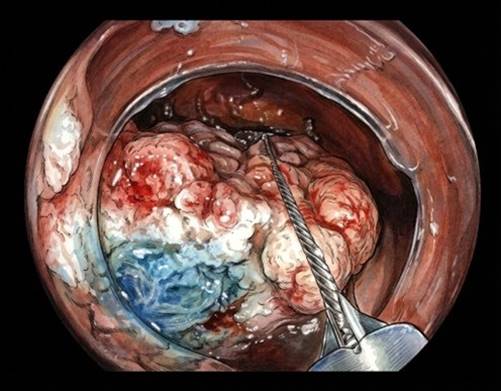

Disección submucosa endoscópica (DSE): microcirugía desde dentro

La DSE se parece a una microcirugía. Se inyecta para separar las capas de la pared del colon y, con un bisturí especial, se va diseccionando el tejido hasta liberar la lesión en una sola pieza. Su principal ventaja es la resección en bloque, que permite al patólogo estudiar márgenes e invasión con mucha más precisión; cuando se logra una resección completa, las recidivas son muy infrecuentes: casi nulas, de hecho.

Recientemente, un ensayo clínico que comparó DSE frente a RME en pólipos grandes de colon mostró que la DSE prácticamente elimina las recurrencias en la zona tratada, aunque a costa de procedimientos más largos, más complicaciones y, a menudo, anestesia general e ingreso. El estudio tampoco demostró que se evitaran más cirugías con la DSE. Por eso las guías suelen reservarla para lesiones con alta sospecha de cáncer superficial o para lesiones rectales extensas donde resecar en una pieza aporta un beneficio claro. En la mayoría de los pólipos grandes claramente benignos, una RME o una UEMR de alta calidad sigue siendo una opción excelente. Actualmente, nuestro equipo está finalizando un ensayo clínico comparando ambas técnicas que aportará nuevos datos.